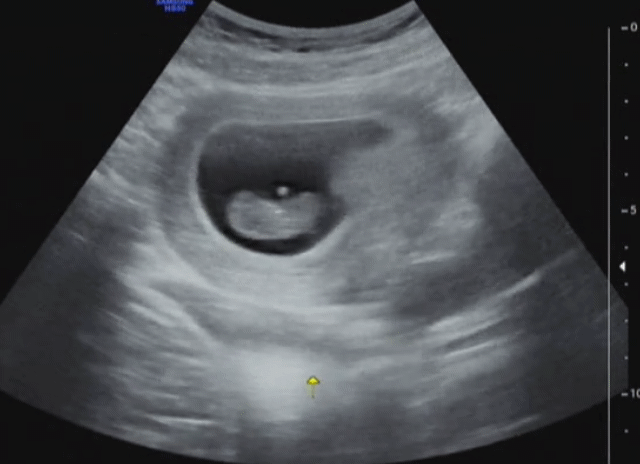

SmartSelect_20181015-141707_Video Player.gif 짠짠이 7주. 꼬물거리는 게 졸귀. 이걸로 임신 소식 많이 전했다.